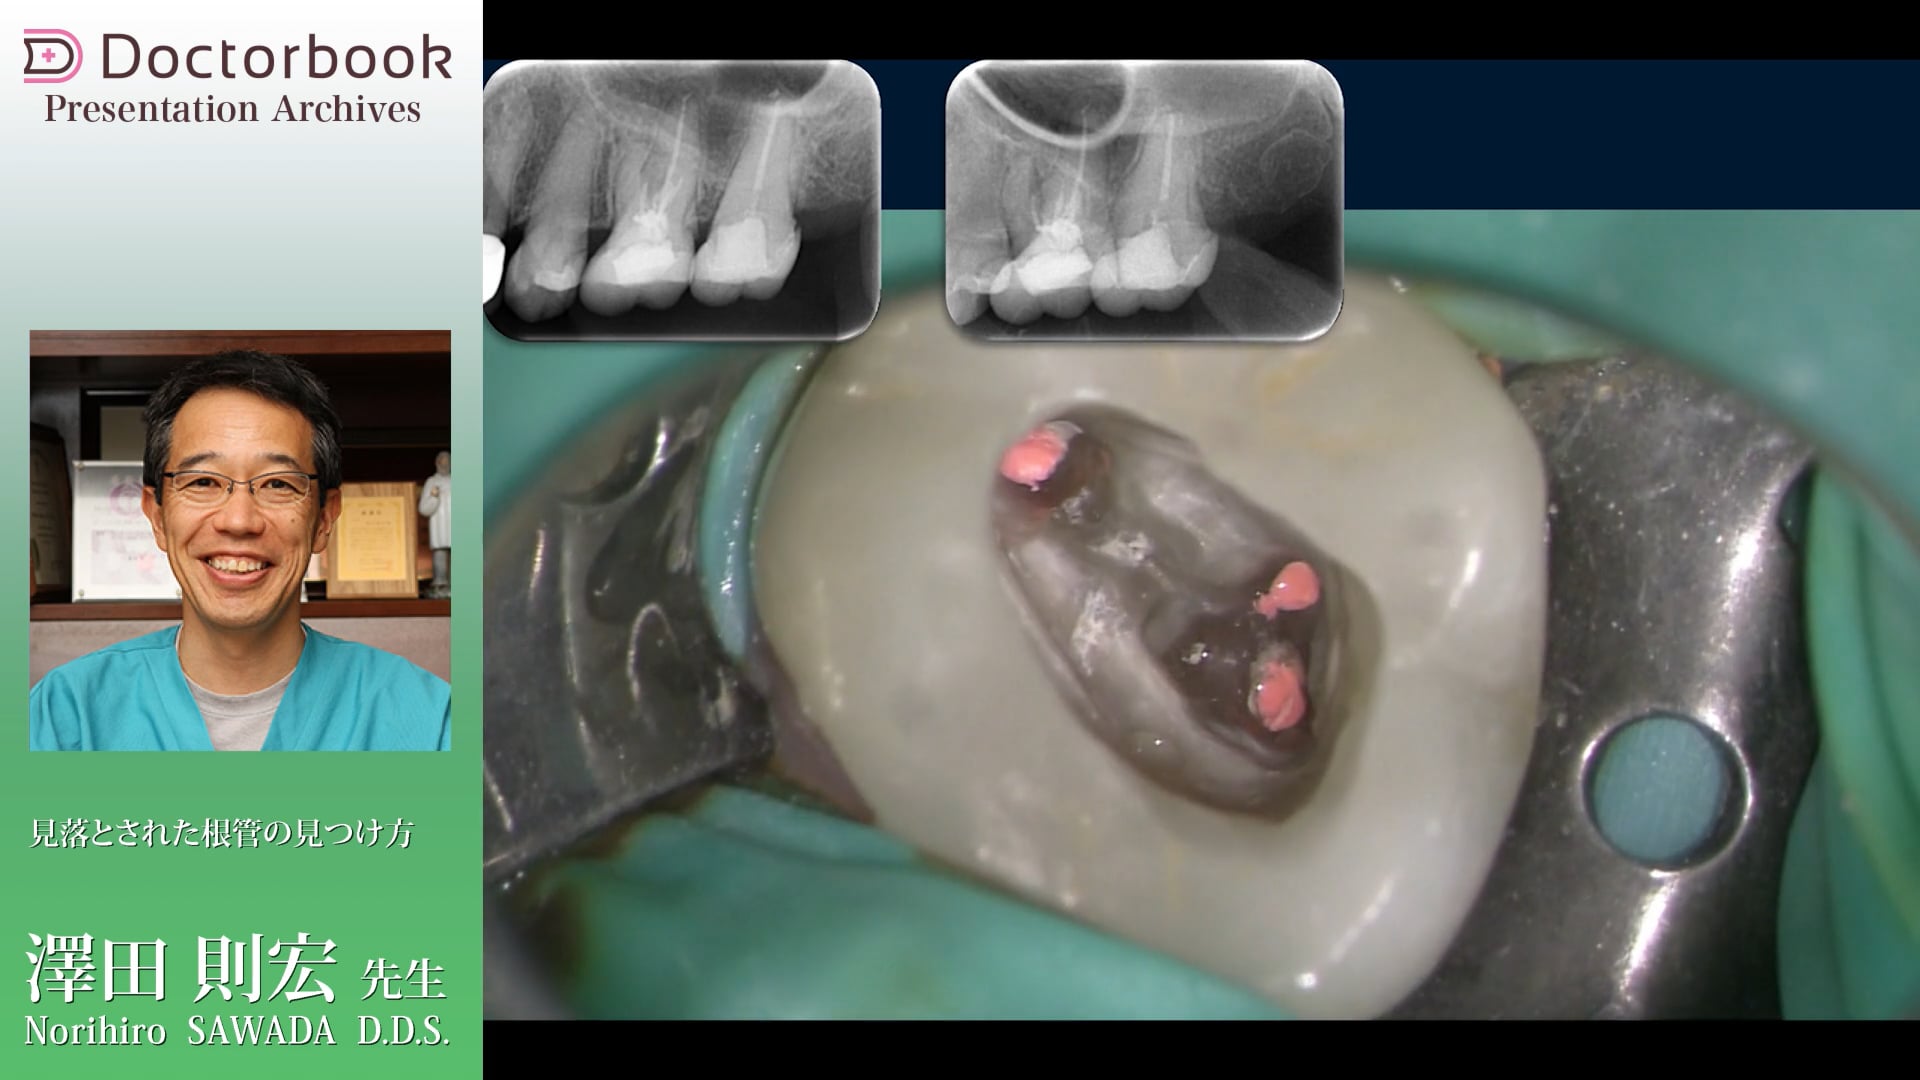

• 1:08 ~ 症例動画

• 4:46 ~ 髄床底を明示

• 5:22 ~ 穿孔の確認

• 7:26 ~ 近心頬側根管発見

• 8:06 ~ MB2発見

• 根管治療を行っていくとき、デンタルX線写真では見える根管がいざ開けたときに見つからないことはありませんか?

特に見にくく器具が操作しにくい近心根管ではそういったことが起きやすいと思います。

今回は東京都新宿区でご開業の澤田則宏先生にマイクロでの治療中の動画から未発見根管の見つけ方をお話していただきました。

パーフォレーション部のGPの除去、折れたリーマーの除去など非常に繊細な部分の治療も動画で丁寧にまとめてくださっています。